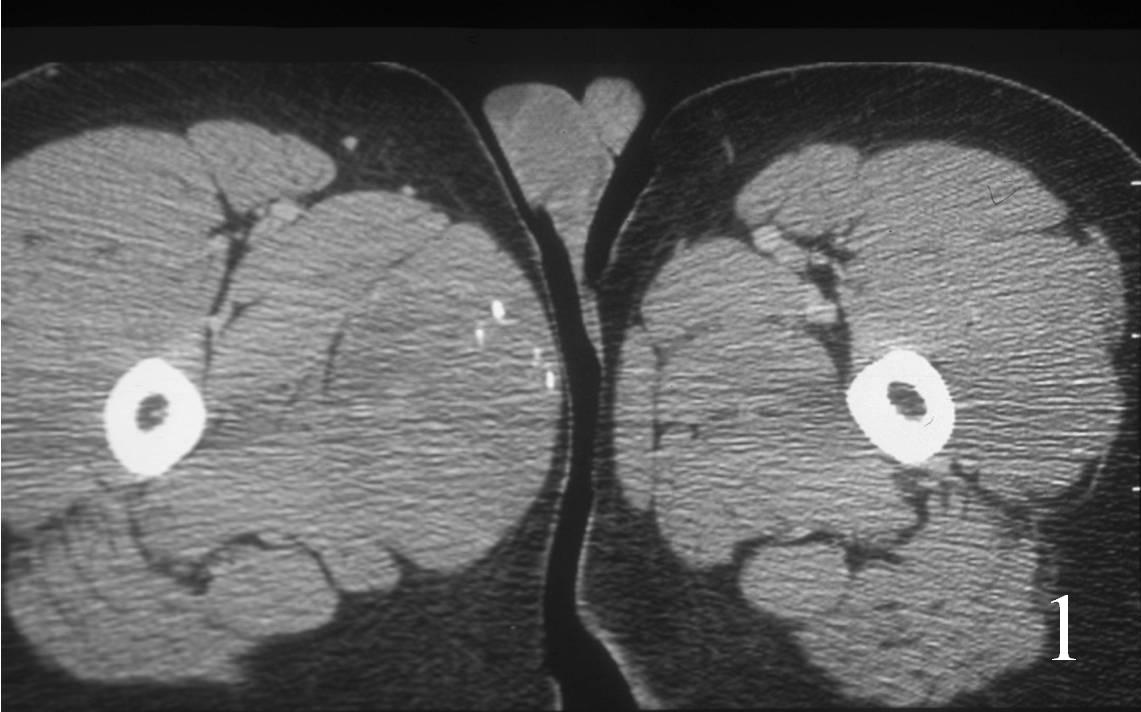

CT

• Good for detecting bone involvement (Fig. 1)

• Isointense to muscle